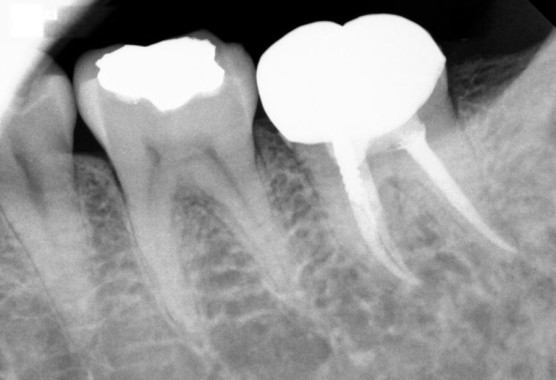

[2022. 06. 27 신경치료 소독 중]

부분신경치료된 부분을 깨끗하게 제거하고 난 모습입니다.

후방부 금이간 부분이 보이시죠?

기존 임시치아를 했던 부분을 제거하고 교합을 낮추고 휴식기를 줬습니다.

증상은 하루가 다르게 좋아졌습니다.